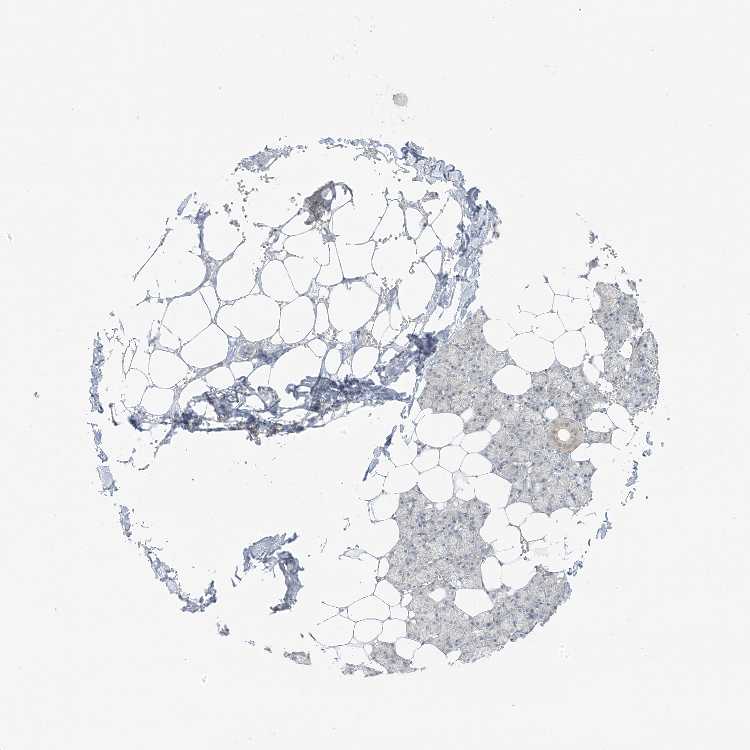

SALIVARY GLAND - Antibody stainingi

Antibody staining in the annotated cell types in the current human tissue is reported as not detected, low, medium, or high, based on conventional immunohistochemistry profiling in selected tissues. This score is based on the combination of the staining intensity and fraction of stained cells.

Each image is clickable and will lead to virtual microscopy that enables deeper exploration of all samples and also displays staining intensity scores, fraction scores and subcellular localization as well as patient and tissue information for each sample.

Antibody HPA034625

Glandular cells Not detected